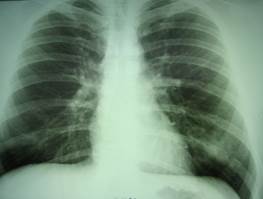

| Кеуде қ уысы ағ заларының рентгенограммасын интерпретациялау

| 1, 0

| 0, 5

|